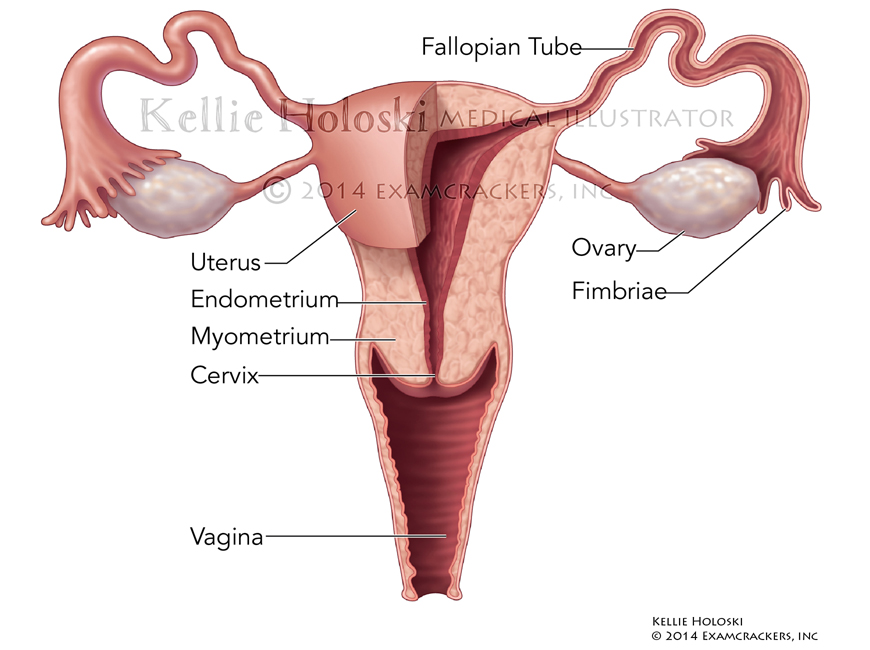

Uterus,

Adobe Photoshop

Published in Examkrackers MCAT Manuals 9th Edition by Jonathan Orsay;

©Osote Publishing -